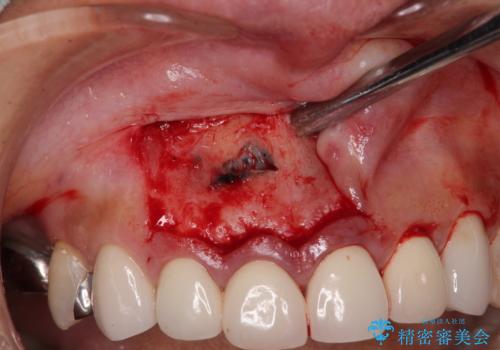

上顎前歯の根尖病変に痛みがありましたが、既に前歯が補綴治療済みであっため、外科的歯内療法(歯根端切除術)を行うことで解決することとしました。

- 外科手術のため、術後に痛みや腫れ、違和感を伴います